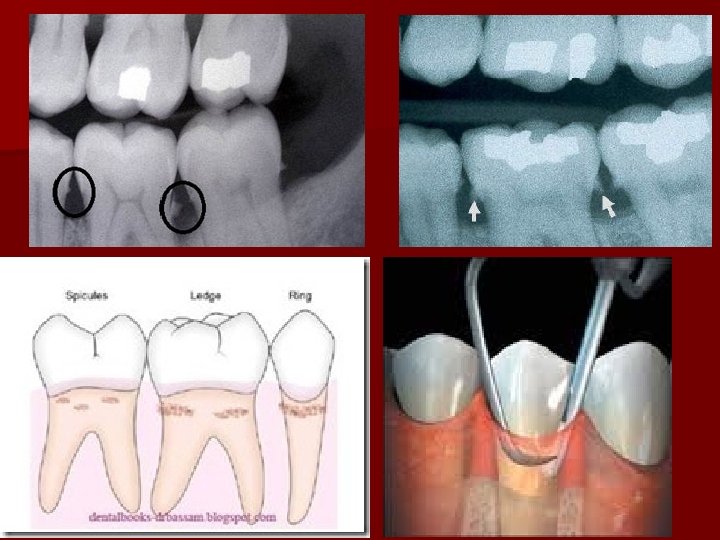

Subgingival calculus is brown to greenish black in color and it’s located below the crest of marginal gingiva, detection requires careful examination with an explorer. It is usually firmly attached to the tooth surface.

Attachment to the tooth surface n n Attachment by means of an organic pellicle which is also calcified. Penetration of calculus bacteria into cementum (this mode is not accepted by some investigators). Mechanical locking into surface irregularities, such as resorption lacunae and caries. Close adaptation of calculus undersurface depressions to the gently sloping mounds of the cementum surface.